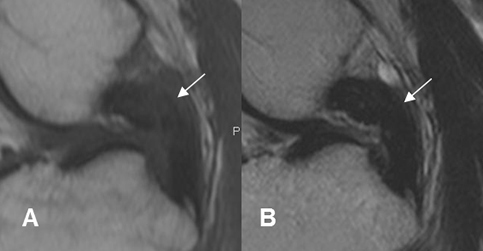

Fig 114. Ruptura del LCP.

A: RM sagital en T1 y B: RM sagital en T2. Solución de continuidad del LCP en su tercio proximal, por ruptura.